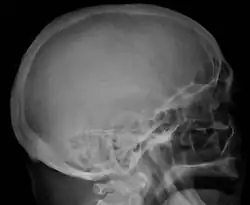

Skull X-ray showing multiple lucencies due to multiple myeloma -

The diagnostic examination of a person with suspected multiple myeloma typically includes a skeletal survey. This is a series of X-rays of the skull, axial skeleton, and proximal long bones. Myeloma activity sometimes appears as "lytic lesions" (with local disappearance of normal bone due to resorption) or as "punched-out lesions" on the skull X-ray ("raindrop skull"). Lesions may also be sclerotic, which is seen as radiodense.[76] Overall, the radiodensity of myeloma is between −30 and 120 Hounsfield units (HU).[77] Magnetic resonance imaging is more sensitive than simple X-rays in the detection of lytic lesions. An MRI may supersede a skeletal survey, especially when vertebral disease is suspected. Occasionally, a CT scan is performed to measure the size of soft-tissue plasmacytomas. Nuclear Medicine Bone scans are typically not of any additional value in the workup of people with myeloma (no new bone formation; lytic lesions not well visualized on nuclear bone scan).

Bone pain affects almost 70% of people with multiple myeloma and is one of the most common symptoms.[2]: 653 [23] Myeloma bone pain usually involves the spine and ribs and worsens with activity. Persistent, localized pain may indicate a pathological bone fracture. Involvement of the vertebrae may lead to spinal cord compression or kyphosis. Myeloma bone disease is due to the overexpression of receptor activator for nuclear factor κ B ligand (RANKL) by bone marrow stroma. RANKL activates osteoclasts, which resorb bone. The resultant bone lesions are lytic (cause breakdown) in nature. They are best seen in plain radiographs, which may show "punched-out" resorptive lesions (including the "raindrop" appearance of the skull on radiography). The breakdown of bone also leads to the release of calcium ions into the blood, leading to hypercalcemia and its associated symptoms.[24]